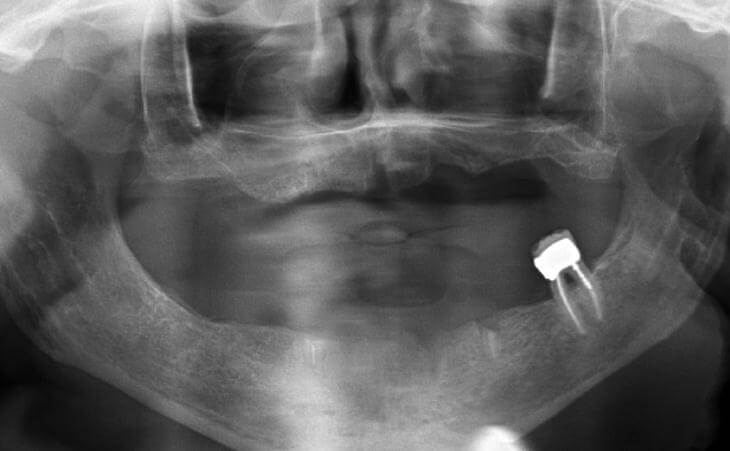

Patient has been missing lower left teeth for years. Developed large ridge defect from not having teeth. Pre surgical CT scan shows thin ridge with inadequate bone volume to place implants. Ridge bone graft was done. Special covering placed and secured. CT scan after 4 months of healing. Final post implant placement x-ray.